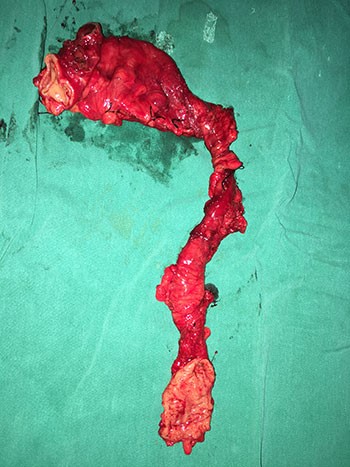

Colonoscopy did not show any structural abnormality. Rectal biopsies showed the normal presence of ganglion cells. After four months, resection of the distal one-third of the transverse colon, splenic flexure, descending colon and sigmoid colon was done with primary transverse colon rectal anastomosis (Figure 3).

Figure 3. Resected specimen of left hemicolectomy showing dilated proximal part and the narrowed segment.

Patient convalesced well and was discharged home on postoperative day 10 without complication. Histopathological examination of resected specimen revealed absence of ganglionic cells with large unmyelinated nerve fibres in the narrowed segment. Both proximal and distal margins showed normal ganglionic cells and nerve plexus confirming a diagnosis of zonal colonic aganglionosis (Figure 4).